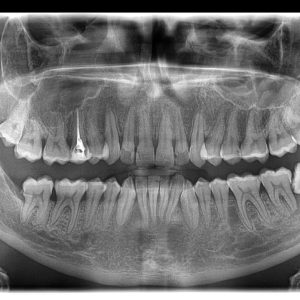

2D snimanje zuba

Ortopan

- Ortopan (ortopantomografija) – panoramska 2D radiografska tehnika koja u jednom snimku prikazuje obe vilice, sve zube i korenove, vilične zglobove i okolne koštane strukture.